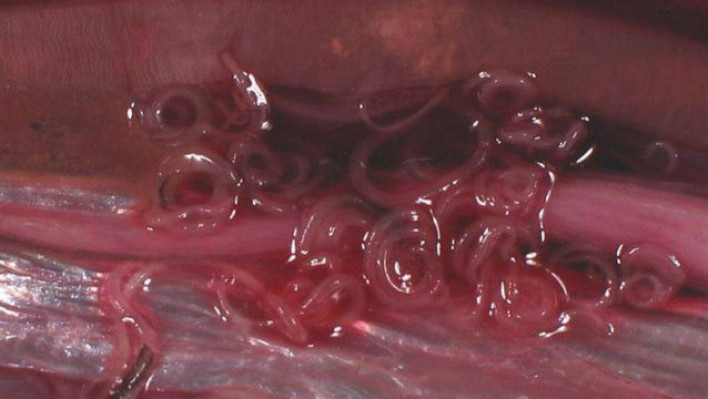

Հյուսիսային Կորեայից Հարավային Կորեա փախած զինվորը գտնվում է բժիշկների տակ անգիտակից վիճակում և արհեստական շնչառությամբ:  Հարավկորեական բժիշկները նրա բուժմամբ են զբաղված և փորձում են կյանքի վերադարձնել: Վիրաբույժները նրա օրգանիզմից տասնյակ որդեր են հեռացրել, որոնցից մի քանիսի  երկարությունը հասել է մոտ 30 սմ-ի, այս մասին հաղորդում է  Fox News-ը: Ինչպես հաղորդում է աղբյուրը, այս պահին զինվորի վիճակը կայուն է: Զինծառայողը փախել է Հյուսիսային Կորեայից դեպի Հարավային Կորեա է: Փախչող զինվորի վրա կրակել էին մոտ 40 անգամ: